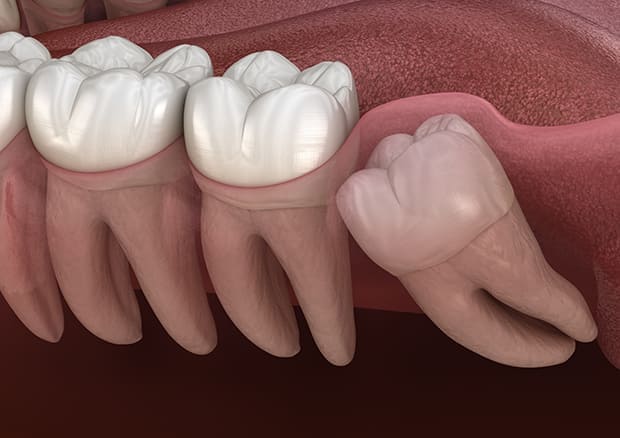

水平埋伏の親知らず

歯茎の中で完全に横に生えてしまうタイプです。

この親知らずを水平埋伏智歯と言います。このタイプはほとんどが下顎のケースです。真横に生えているので抜歯の際は難易度が高く2~3つに砕いて分けて抜歯をします。